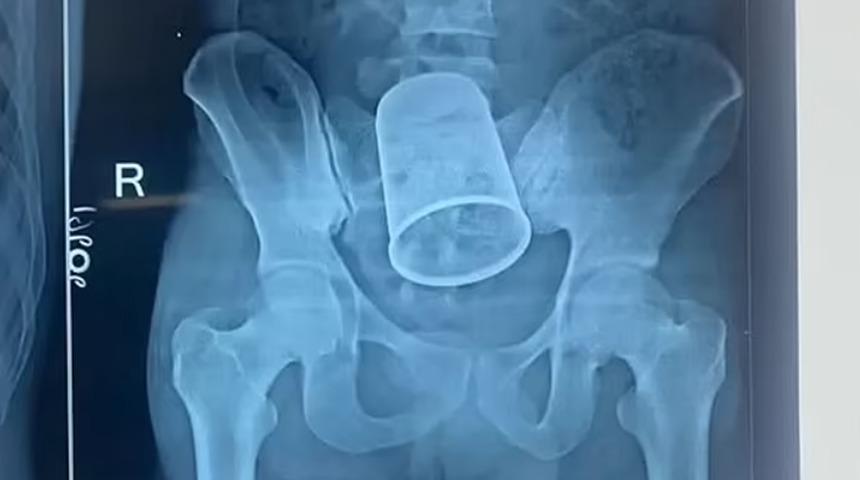

Yerel basına göre, 7 cm çapındaki çelik bardak bağırsak hareketlerini engellediği için acı veren mide ağrıları çekiyordu. Taramalar, 14 cm uzunluğundaki bardağın vücudunun içinde olduğunu ortaya çıkardı ve onu karnından çıkarmak için iki buçuk saat bıçağın altında kaldı.